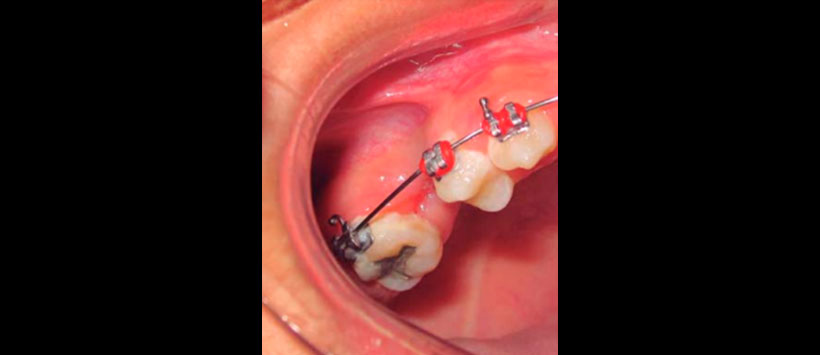

Paciente pediátrica de 12 años de edad referida a la Clínica de Cirugía Oral y Maxilofacial de la Universidad Veracruzana región Poza Rica-Tuxpan, con diagnóstico de quiste maxilar derecho, sin antecedentes relevantes en su historia médica para el padecimiento actual. Clínicamente presentaba aumento de volumen en región geniana derecha, intraoralmente en maxilar derecho, expansión cortical en región de premolares, tumefacción circunscrita, bien delimitada, indurada, coloración similar a la mucosa adyacente, presencia de segundo molar deciduo con una restauración con una corona acero-cromo (Figuras 1 a 3).